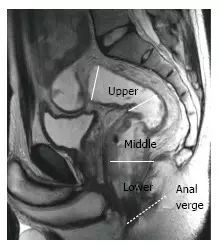

图 2. 根据距肛门边缘的距离,可将直肠分成三段。T2 加权矢状图显示,直肠上段(> 10 厘米),中段(5~10 厘米),和下段(

因预后和手术管理受肿瘤部位的影响,应报告肿瘤高度和长度。矢状位上划线测量肿瘤长度,肿瘤位置是肿瘤最低处至肛缘距离,并分作上中下三段(图 7)。